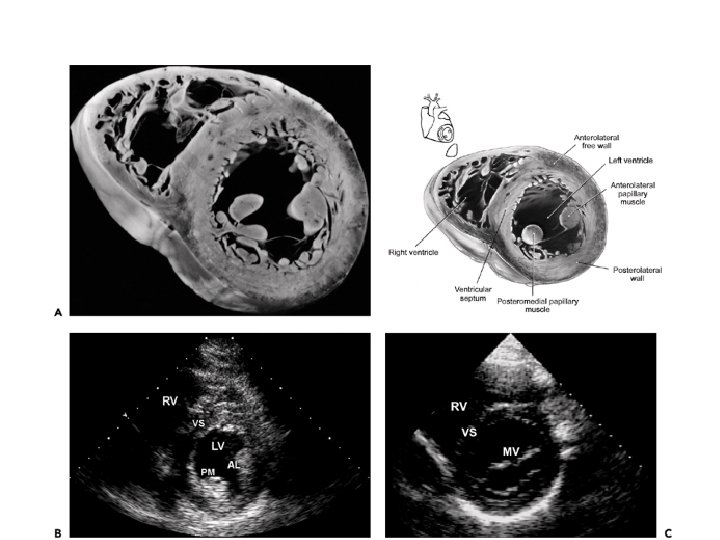

PARASTERNAL SHORT AXIS